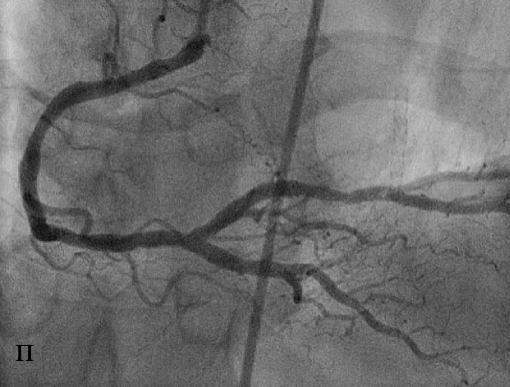

При коронарографии ПКА выявлен выраженный стеноз дистального сегмента ПКА с переходом на устье ЗМЖВ (о). В дистальную треть ПКА с переходом на устье ЗМЖВ был имплантирован стент XienceV, сужение устранено, достигнут хороший ангиографический результат (п).